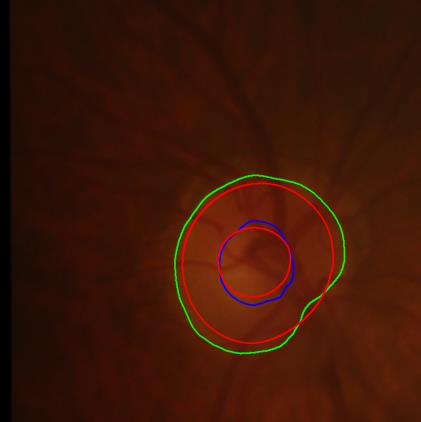

Modern deep neural networks struggle to transfer knowledge and generalize across diverse domains when deployed to real-world applications. Currently, domain generalization (DG) is introduced to learn a universal representation from multiple domains to improve the network generalization ability on unseen domains. However, previous DG methods only focus on the data-level consistency scheme without considering the synergistic regularization among different consistency schemes. In this paper, we present a novel Hierarchical Consistency framework for Domain Generalization (HCDG) by integrating Extrinsic Consistency and Intrinsic Consistency synergistically. Particularly, for the Extrinsic Consistency, we leverage the knowledge across multiple source domains to enforce data-level consistency. To better enhance such consistency, we design a novel Amplitude Gaussian-mixing strategy into Fourier-based data augmentation called DomainUp. For the Intrinsic Consistency, we perform task-level consistency for the same instance under the dual-task scenario. We evaluate the proposed HCDG framework on two medical image segmentation tasks, i.e., optic cup/disc segmentation on fundus images and prostate MRI segmentation. Extensive experimental results manifest the effectiveness and versatility of our HCDG framework.